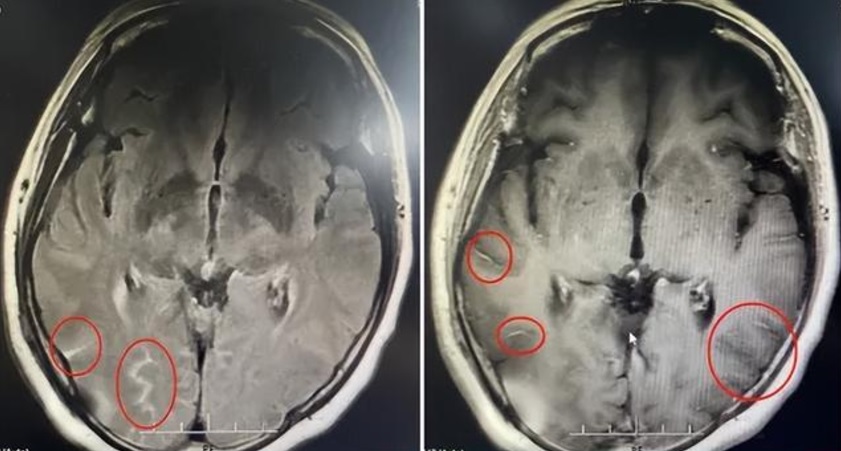

经检查才发现,头痛问题根本不是颈椎毛病所引起,而是感染“隐球菌脑膜炎”;隐球菌是一种真菌,主要会侵犯中枢神经系统,死亡率高。

医生诊断后发现,妇女的颅内压增高,不但挤压了旁边的脑组织,还造成脑中较长颅神经的损伤,导致视力下降、听力损伤等不可逆的伤害。

幸好经过手术以及一系列的治疗,妇女的头痛症状好转,左眼视力也恢复正常。